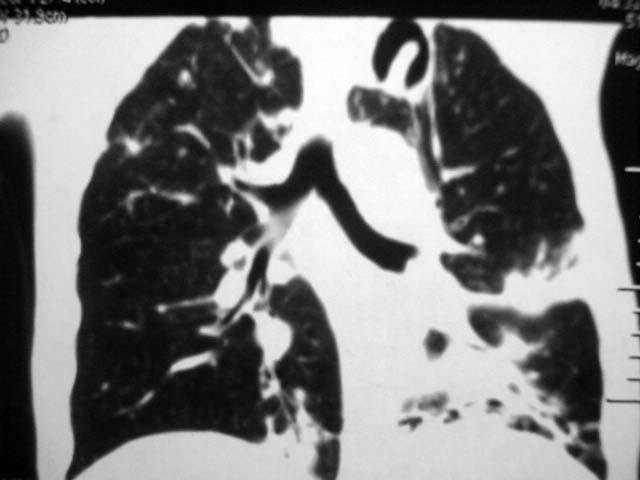

男,52岁,发热2月,糖尿病史。

抗结核治疗irpz方案,血糖未治疗,空腹15.9左右。症状无好转,左胸痛。

复查ct

2、双肺见多发片状及结节状高密度影,大多数病灶中心均见“空泡征”。

3、纵隔内淋巴结肿大。

结果:两肺继发性肺结核并曲霉菌感染。